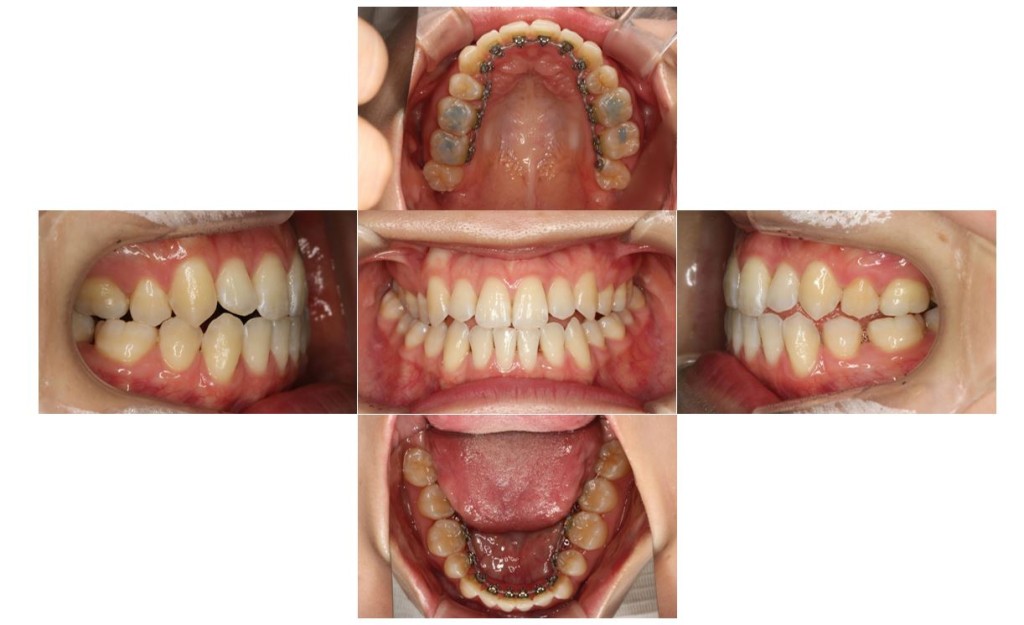

| 主訴 | 下の歯が、上の歯より前に出ていて顎が出ているのが気になる。受け口を治したい。でこぼこもあり歯磨きにしくいので、虫歯予防のためにも綺麗に並べたい。 |

| 治療期間 | 2年2ヶ月(29回) |

| 抜歯 | 有(左上4、左下5、上下親知らず4本) |

| 矯正の装置 | 裏側矯正(舌側矯正) |